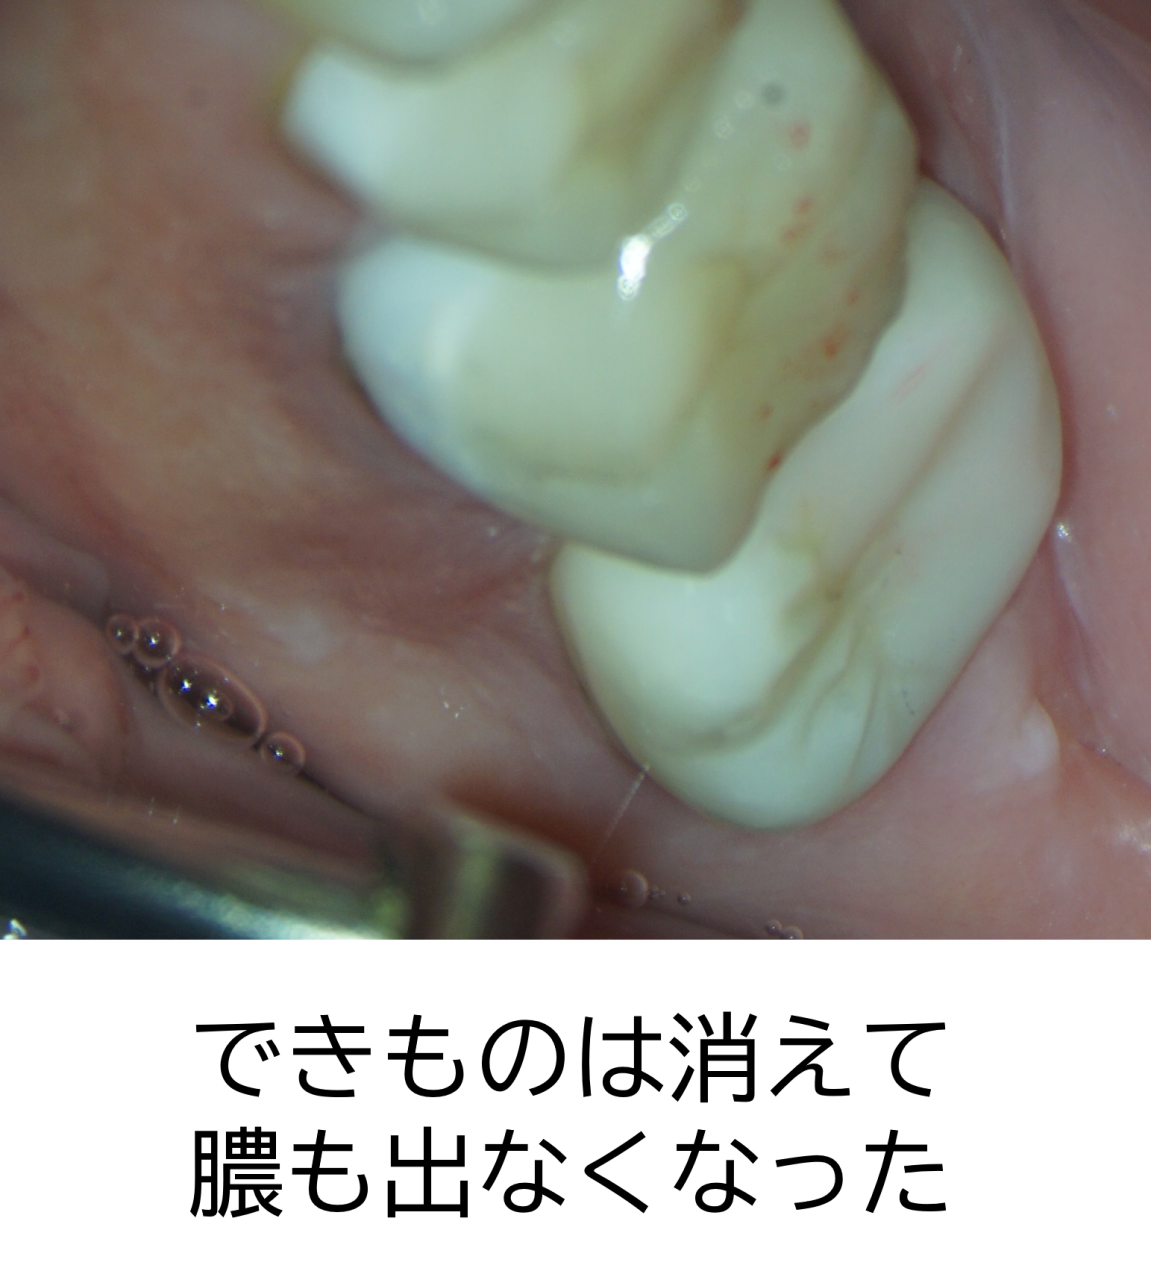

その後、かぶせ物を行いました。まだ跡は見られますが、最初にあったできものは無くなり、膿も出なくなっています。患者様は非常に喜ばれました。

食事も痛みもなく快適ということで、このまま経過観察になりました。